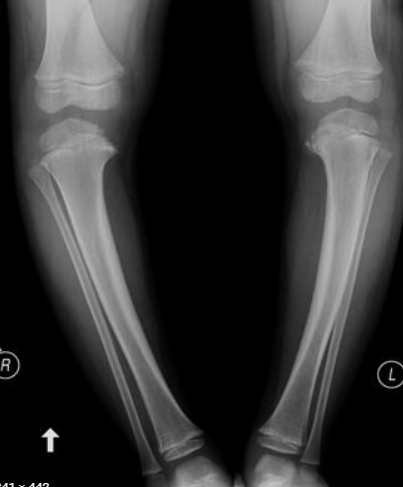

Quais desvios?

VARO + FLEXO (procurvato)+ ROTAÇÃO INTERNA (tíbia)

Clínica? Comorbidade associada?

Deformidade na tíbia (mais arqueada)

Abertura lateral na fase de balanço

Radiografias (5 achados)?

Varo na metáfise proximal da tíbia;

Alargamento e irregularidade da fise medial;

Epífise ossificada e curvada (slope) para medial;

Bico proeminente na METÁFISE medial;

Subluxação lateral da tíbia proximal

OBS: No adolescente NÃO HÁ BICO MEDIAL